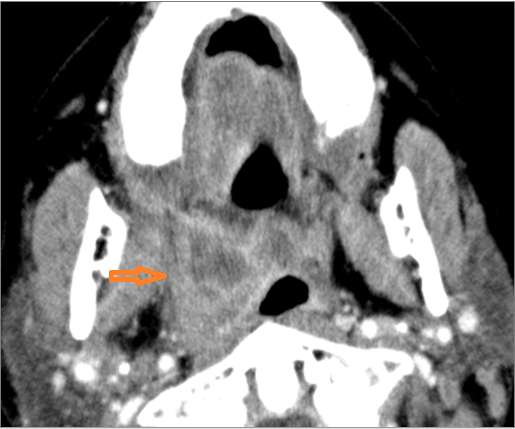

Major Salivary Glands

There is significant abnormality of the parotid, submandibular or sublingual glands that would be an alternate explanation for the patient’s symptoms.